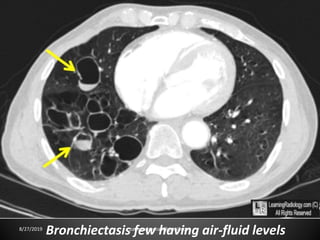

Bronchiectasis: localized bronchial dilatation.

The diagnosis is based on a combination of the

following findings:

-bronchial dilatation (signet-ring sign)

-bronchial wall thickening

-lack of normal tapering with visibility of airways in

the peripheral lung

-mucus retention in the bronchial lumen

-associated atelectasis and sometimes air trapping

8/27/2019 zannatulrayhan@gmail.com

Bronchiectasis few having air-fluid levels8/27/2019 zannatulrayhan@gmail.com